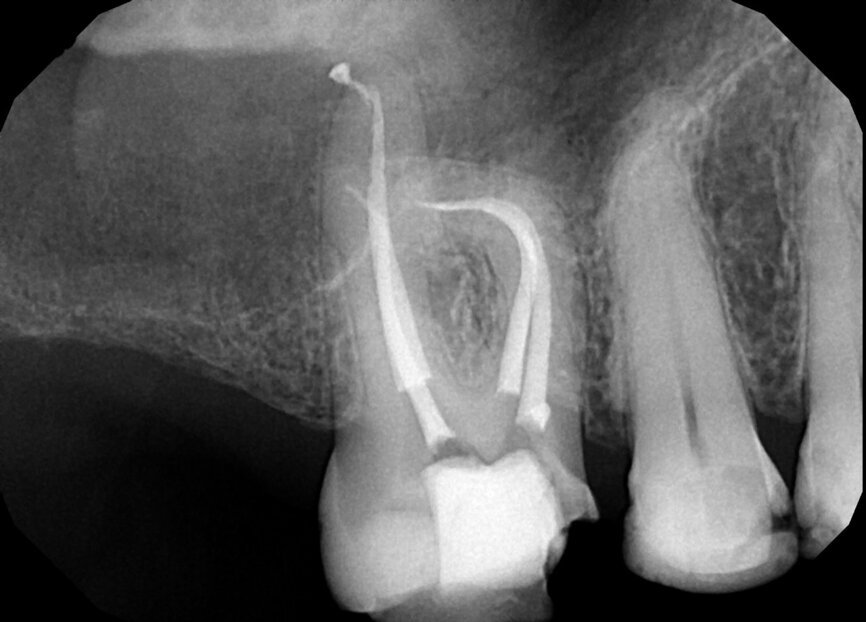

Fig. 18a: Note the expert management of the apical constriction and the acute curvature of the MB root. (Courtesy of Dr. Nestor Cohenca)

Fig. 18b: Note the expert management of the apical constriction and the acute curvature of the MB root. (Courtesy of Dr. Nestor Cohenca)

Fig. 18c: Note the expert management of the apical constriction and the acute curvature of the MB root (courtesy of Dr. Nestor Cohenca).